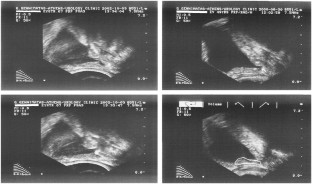

Leventis AK, Shariat SF, Slawin KM . Local recurrence after radical prostatectomy: correlation of US features with prostatic fossa biopsy findings. Radiology 2001; 219: 432–439.